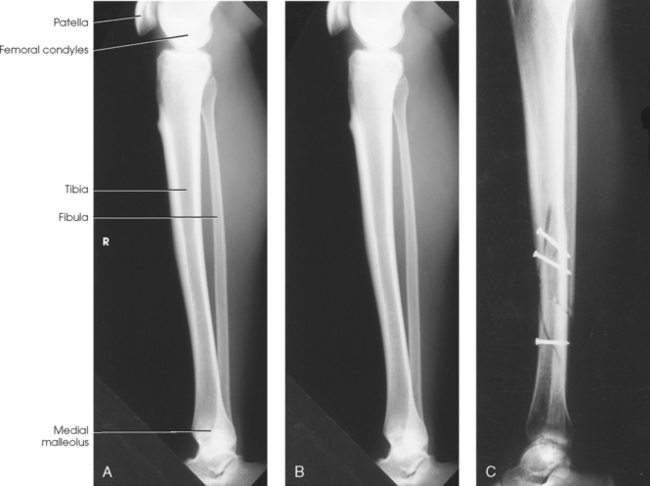

Structures shown: The resulting image shows the tibia, fibula, and adjacent joints (Fig. 6-112).

Fig. 6-112 A, AP tibia and fibula. Long leg length prevented showing entire leg. A separate knee projection had to be performed on this patient. B, Short leg length allowed entire leg to be shown. Spiral fracture of distal tibia with accompanying spiral fracture of proximal fibula (arrows) is seen. This radiograph shows the importance of including the entire length of a long bone in trauma cases. C, AP tibia and fibula on a 4-year-old with neurofibromatosis.